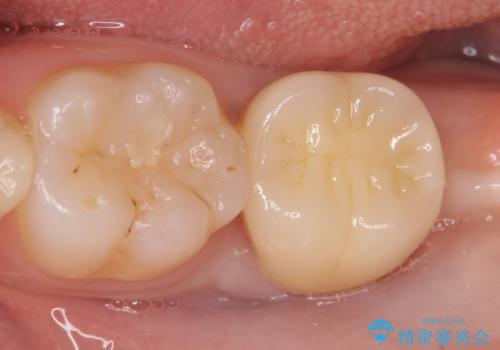

銀歯がしみる PGA(ゴールド)インレーへ 40代女性

- 銀歯がしみることを主訴に来院されました。

銀のつめものを除去したところ、大きなう蝕を認めました。

咬合力が強いため、割れる心配がなく強度の高いPGA(ゴールド)インレーをご希望されました。

治療後はしみなくなり、違和感のない自然な咬み心地にご満足頂けました。

「割れる心配のないゴールドにしたいけれど、目立ってしまうかしら...」と心配されており、不要に歯質を削合しないよう注意を払い最小限の大きさのインレーを装着したところ、「あまり目立たなくて良かった!」とおっしゃって下さいました。